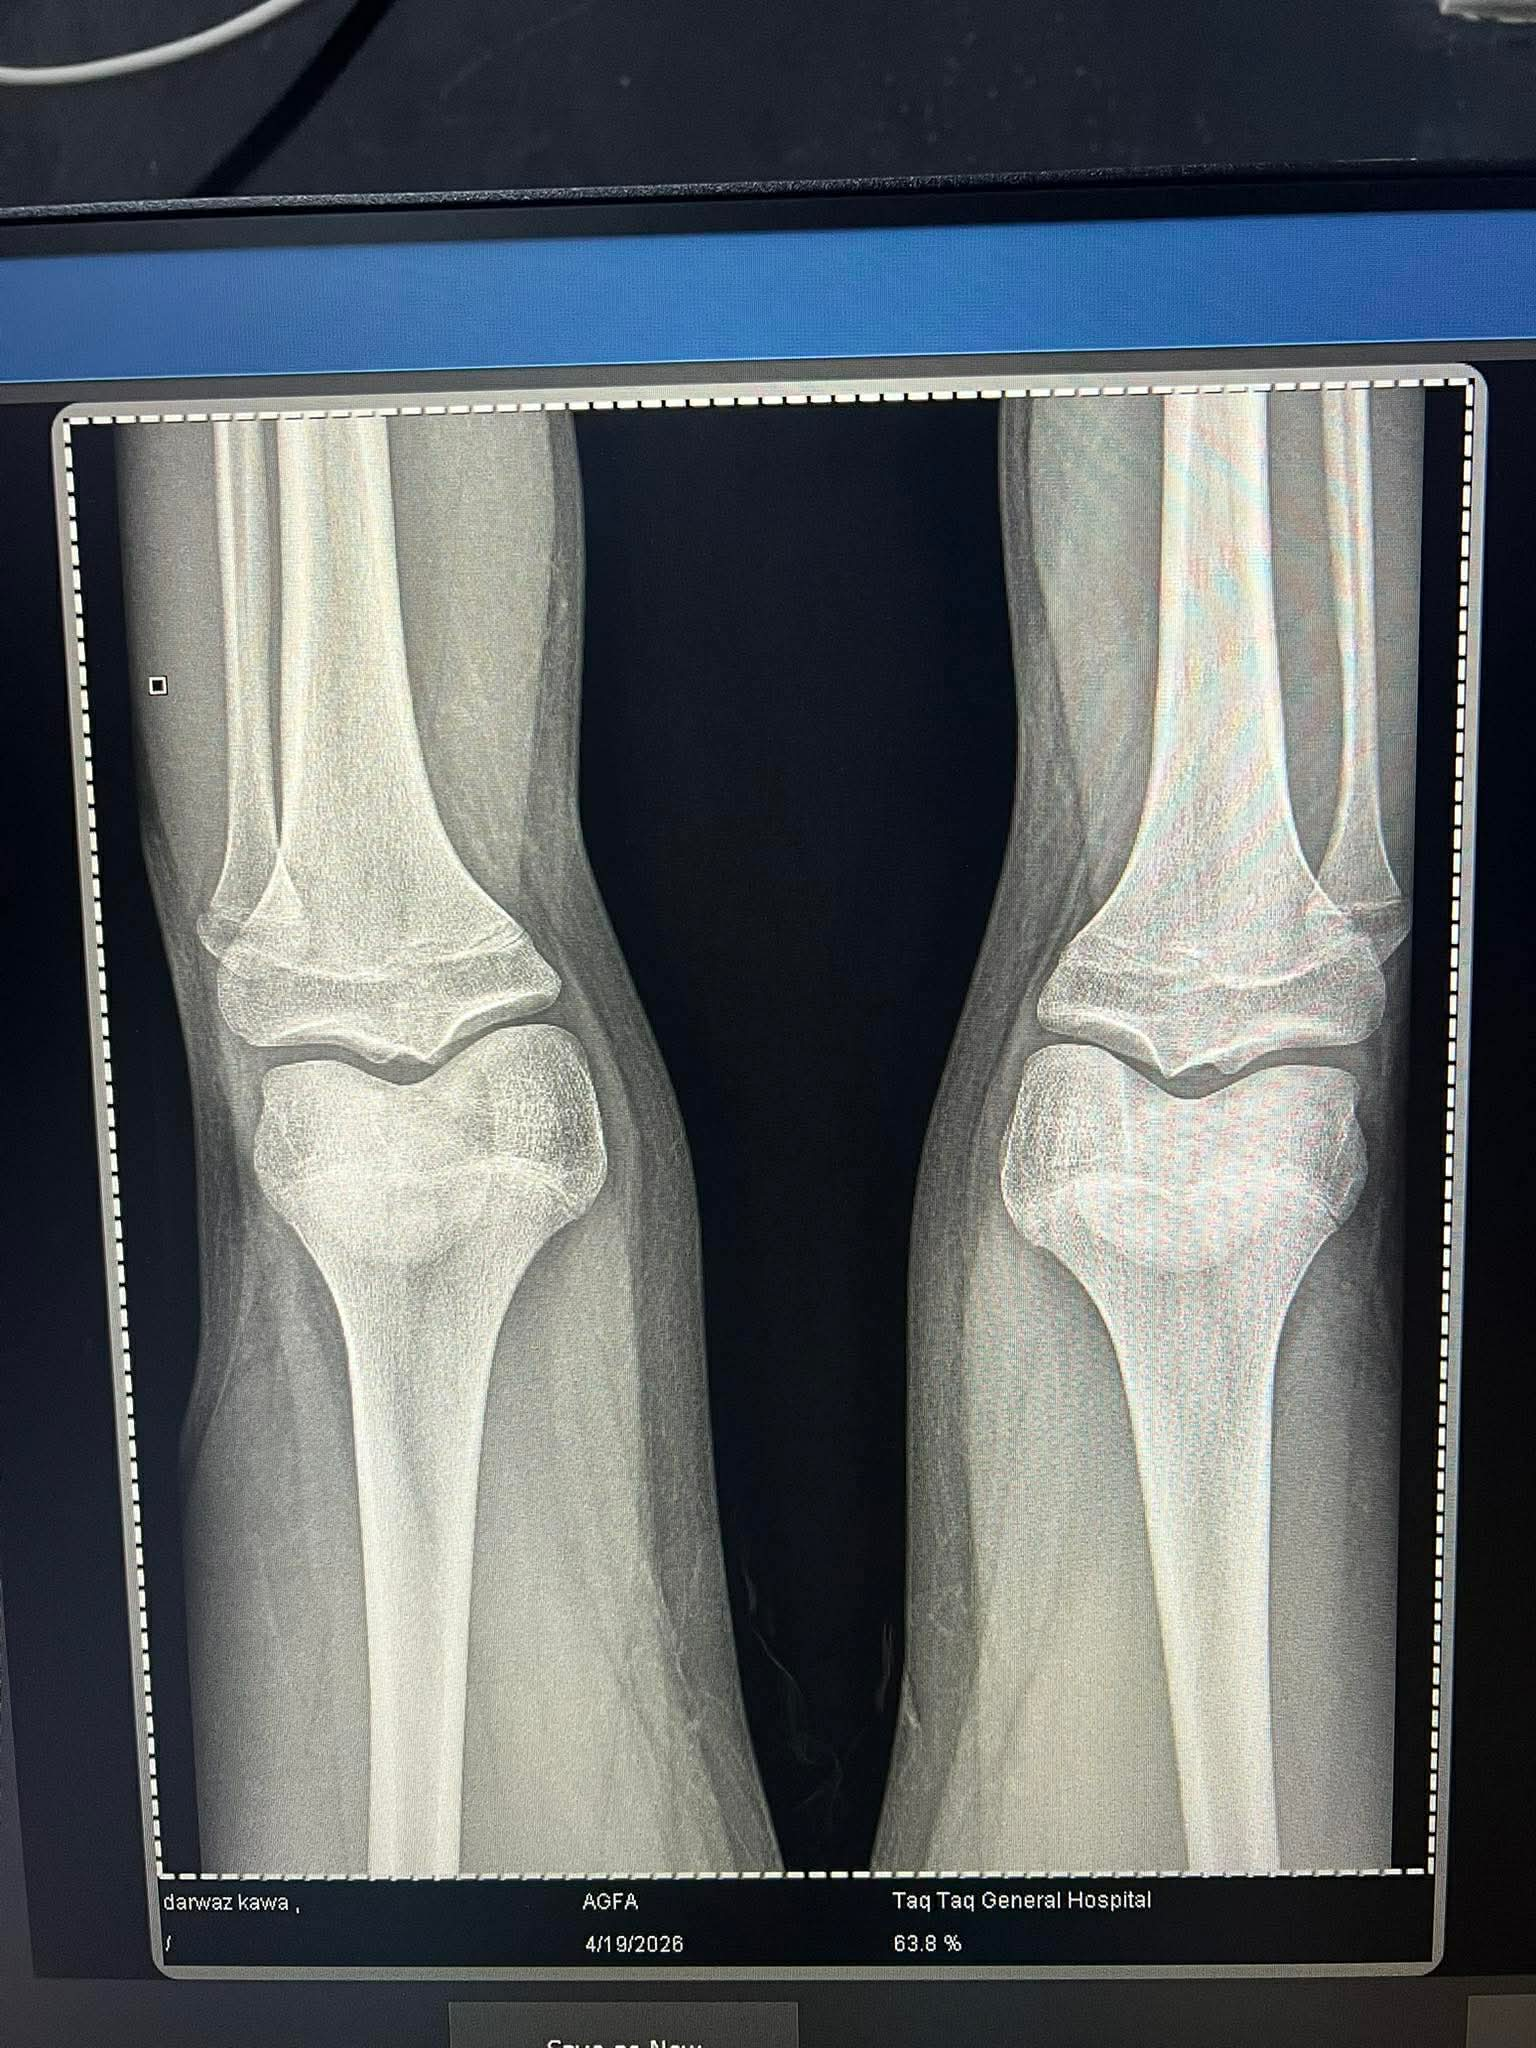

Plates are almost closed doctor said i wont prescribe u ai

I have been diganosed ghd at a time where my g plates are almost fusing in that stage and i told my doctor abt it he said u have come too late i wouldve given u ai if u have came at 14 and said wont prescribe u now its gona ruin the gh ur ok rn nad bla bla:feelsrope::feelsrope::feelsrope::feelsrope::feelsrope::feelsrope::feelsrope: should i get ai myself or its pointless

I have been diganosed ghd at a time where my g plates are almost fusing in that stage and i told my doctor abt it he said u have come too late i wouldve given u ai if u have came at 14 and said wont prescribe u now its gona ruin the gh ur ok rn nad bla bla:feelsrope::feelsrope::feelsrope::feelsrope::feelsrope::feelsrope::feelsrope: should i get ai myself or its pointlessView attachment 4953277

bro e2 at 50pg? ggs no ai will help too late